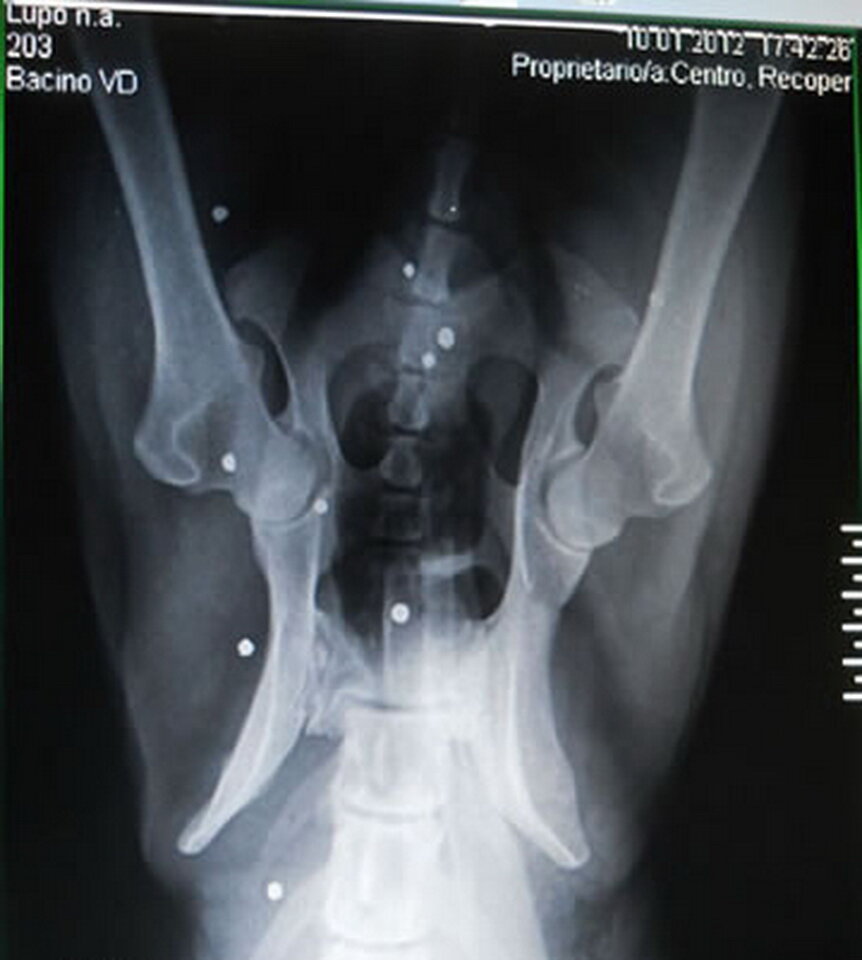

Снимок показал наличие около 35 дробин в теле волка, но выстрел был сделан уже давно